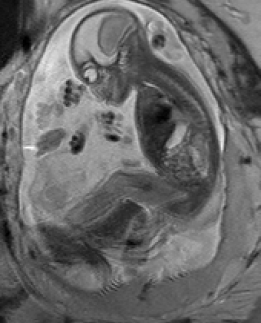

Reconstruction of Fetal Organs: Exemplary PVR and SVR reconstructions under motion introduced by kicking of the fetus are shown in Fig. 11. PVR reconstruction results show an improved visual appearance and less blurring in the region with severe motion artifacts (arrow). An example of a challenging clinical case with a kidney malformation in one of twin fetuses, is shown in Fig. 8. Our clinical partners confirmed that such complications are easier to examine and to quantify after PVR-based reconstruction.

(a) Input

(b) SVR

(c) PVR

Comparative experiments of PVR variants were carried out on 32 fetal MR scans at gestational ages of approximately 20 weeks, presenting with challenging image corruption. Tab. I (a) & (b) show numerical results of evaluating individual stacks before reconstruction (baseline), and the final reconstructed image using square patches, superpixels and multi-scale variants of PVR. Statistical testing between baseline and PVR variants was carried out using paired T-Tests and differences between using fixed or multi-scale and using square patches or superpixels were assessed via Two-factor ANOVA with repeated measures. In Tab. I (a) & (b) the names of PVR variants are marked in bold if statistically significant differences have been found during analysis, i.e., FS and MS and/or Square Patches and Superpixel pairs are bold if the results between them differ significantly.